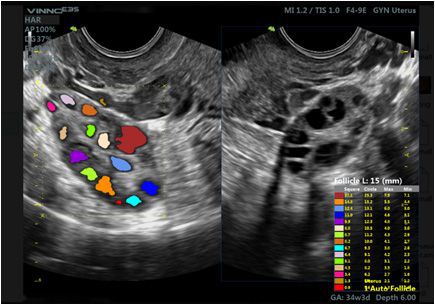

- VAim Follicle: KI-gestützte Vermessung der Follikel